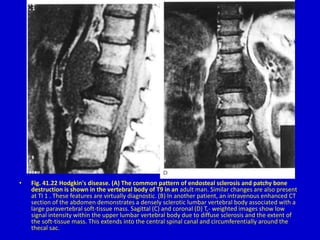

• Fig. 41.22 Hodgkin's disease. (A) The common pattern of

endosteal sclerosis and patchy bone destruction is shown in the

vertebral body of T9 in an adult man. Similar changes are also

present at TI 1 . These features are virtually diagnostic. (B) In

another patient, an intravenous enhanced CT section of the

abdomen demonstrates a densely sclerotic lumbar vertebral body

associated with a large paravertebral soft-tissue mass. Sagittal (C)

and coronal (D) T,- weighted images show low signal intensity

within the upper lumbar vertebral body due to diffuse sclerosis

and the extent of the soft-tissue mass. This extends into the

central spinal canal and circumferentially around the thecal sac.